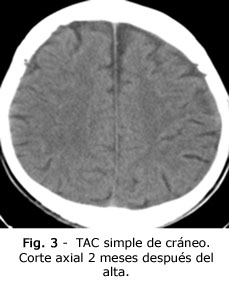

Se decide realizar tratamiento conservador. El esquema terapéutico fue el mismo descrito para el paciente anterior. Además de 12 mg de dexametasona i.v. durante 3 días, hasta suspender de forma gradual en 9 días. Permaneció con internamiento durante 12 días, después continuó con evaluación periódica en consulta ambulatoria, con inhibidores de enzima convertidora de angiotensina (IECA) y estatinas por vía oral. En la TAC simple de cráneo, evolutiva, a los 2 meses, no se evidenció colección subdural (Fig. 3).